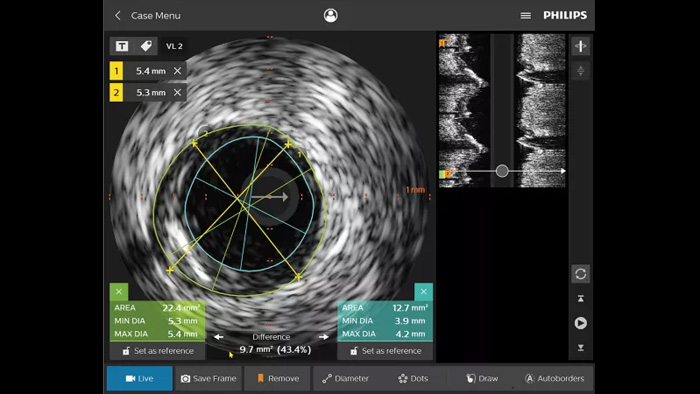

IVUS devices

Intravascular ultrasound (IVUS) is a catheter-based imaging technology that allows physicians to visualize blood vessels from the inside out to aid assessment of presence and extent of disease. IVUS helps to decide, guide and confirm the right interventional treatment for each patient.